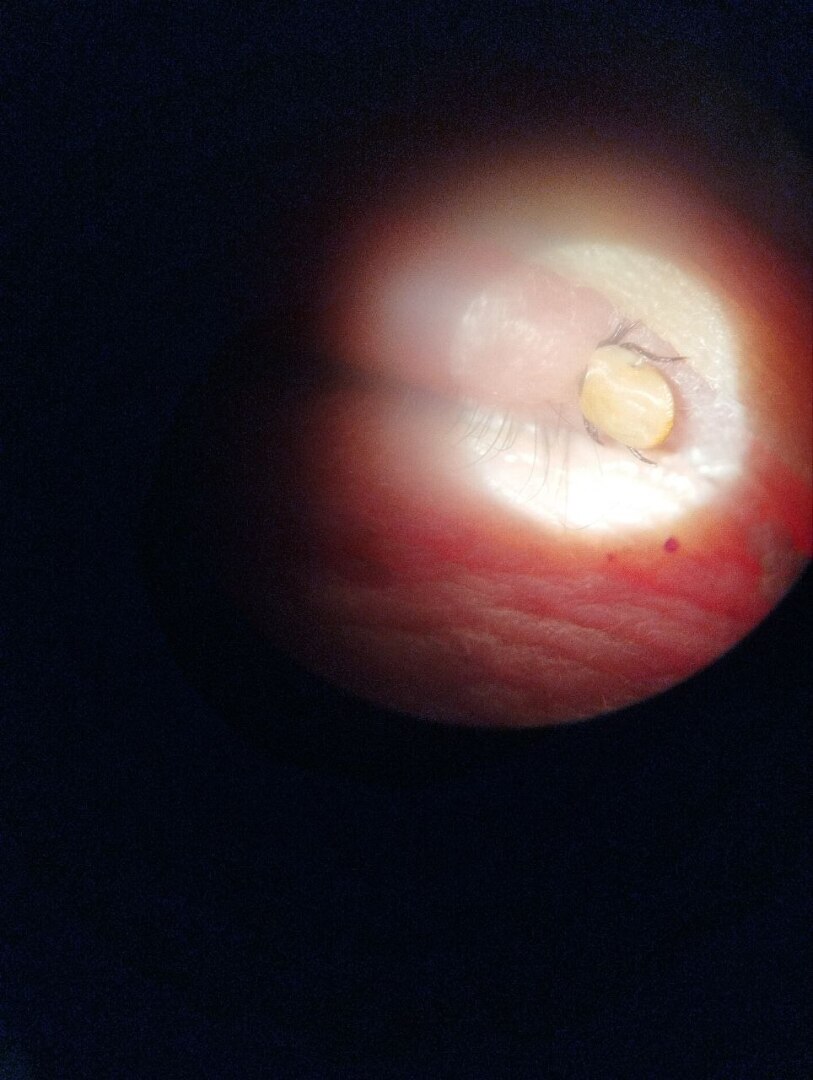

Клещ на верхнем веке.

Данные кадры (смотрите ниже) еще раз подтверждают, что клещу без разницы куда воткнуть свои челюсти.

Куда обратиться за помощью: в поликлинику либо в травпункт. В случае с локализацией укуса в области глаз обращайтесь в глазной травмпункт, не пытайтесь вытащить клеща самостоятельно. Глаз и окологазная область требуют повышенной осторожности при работе с инструментами.